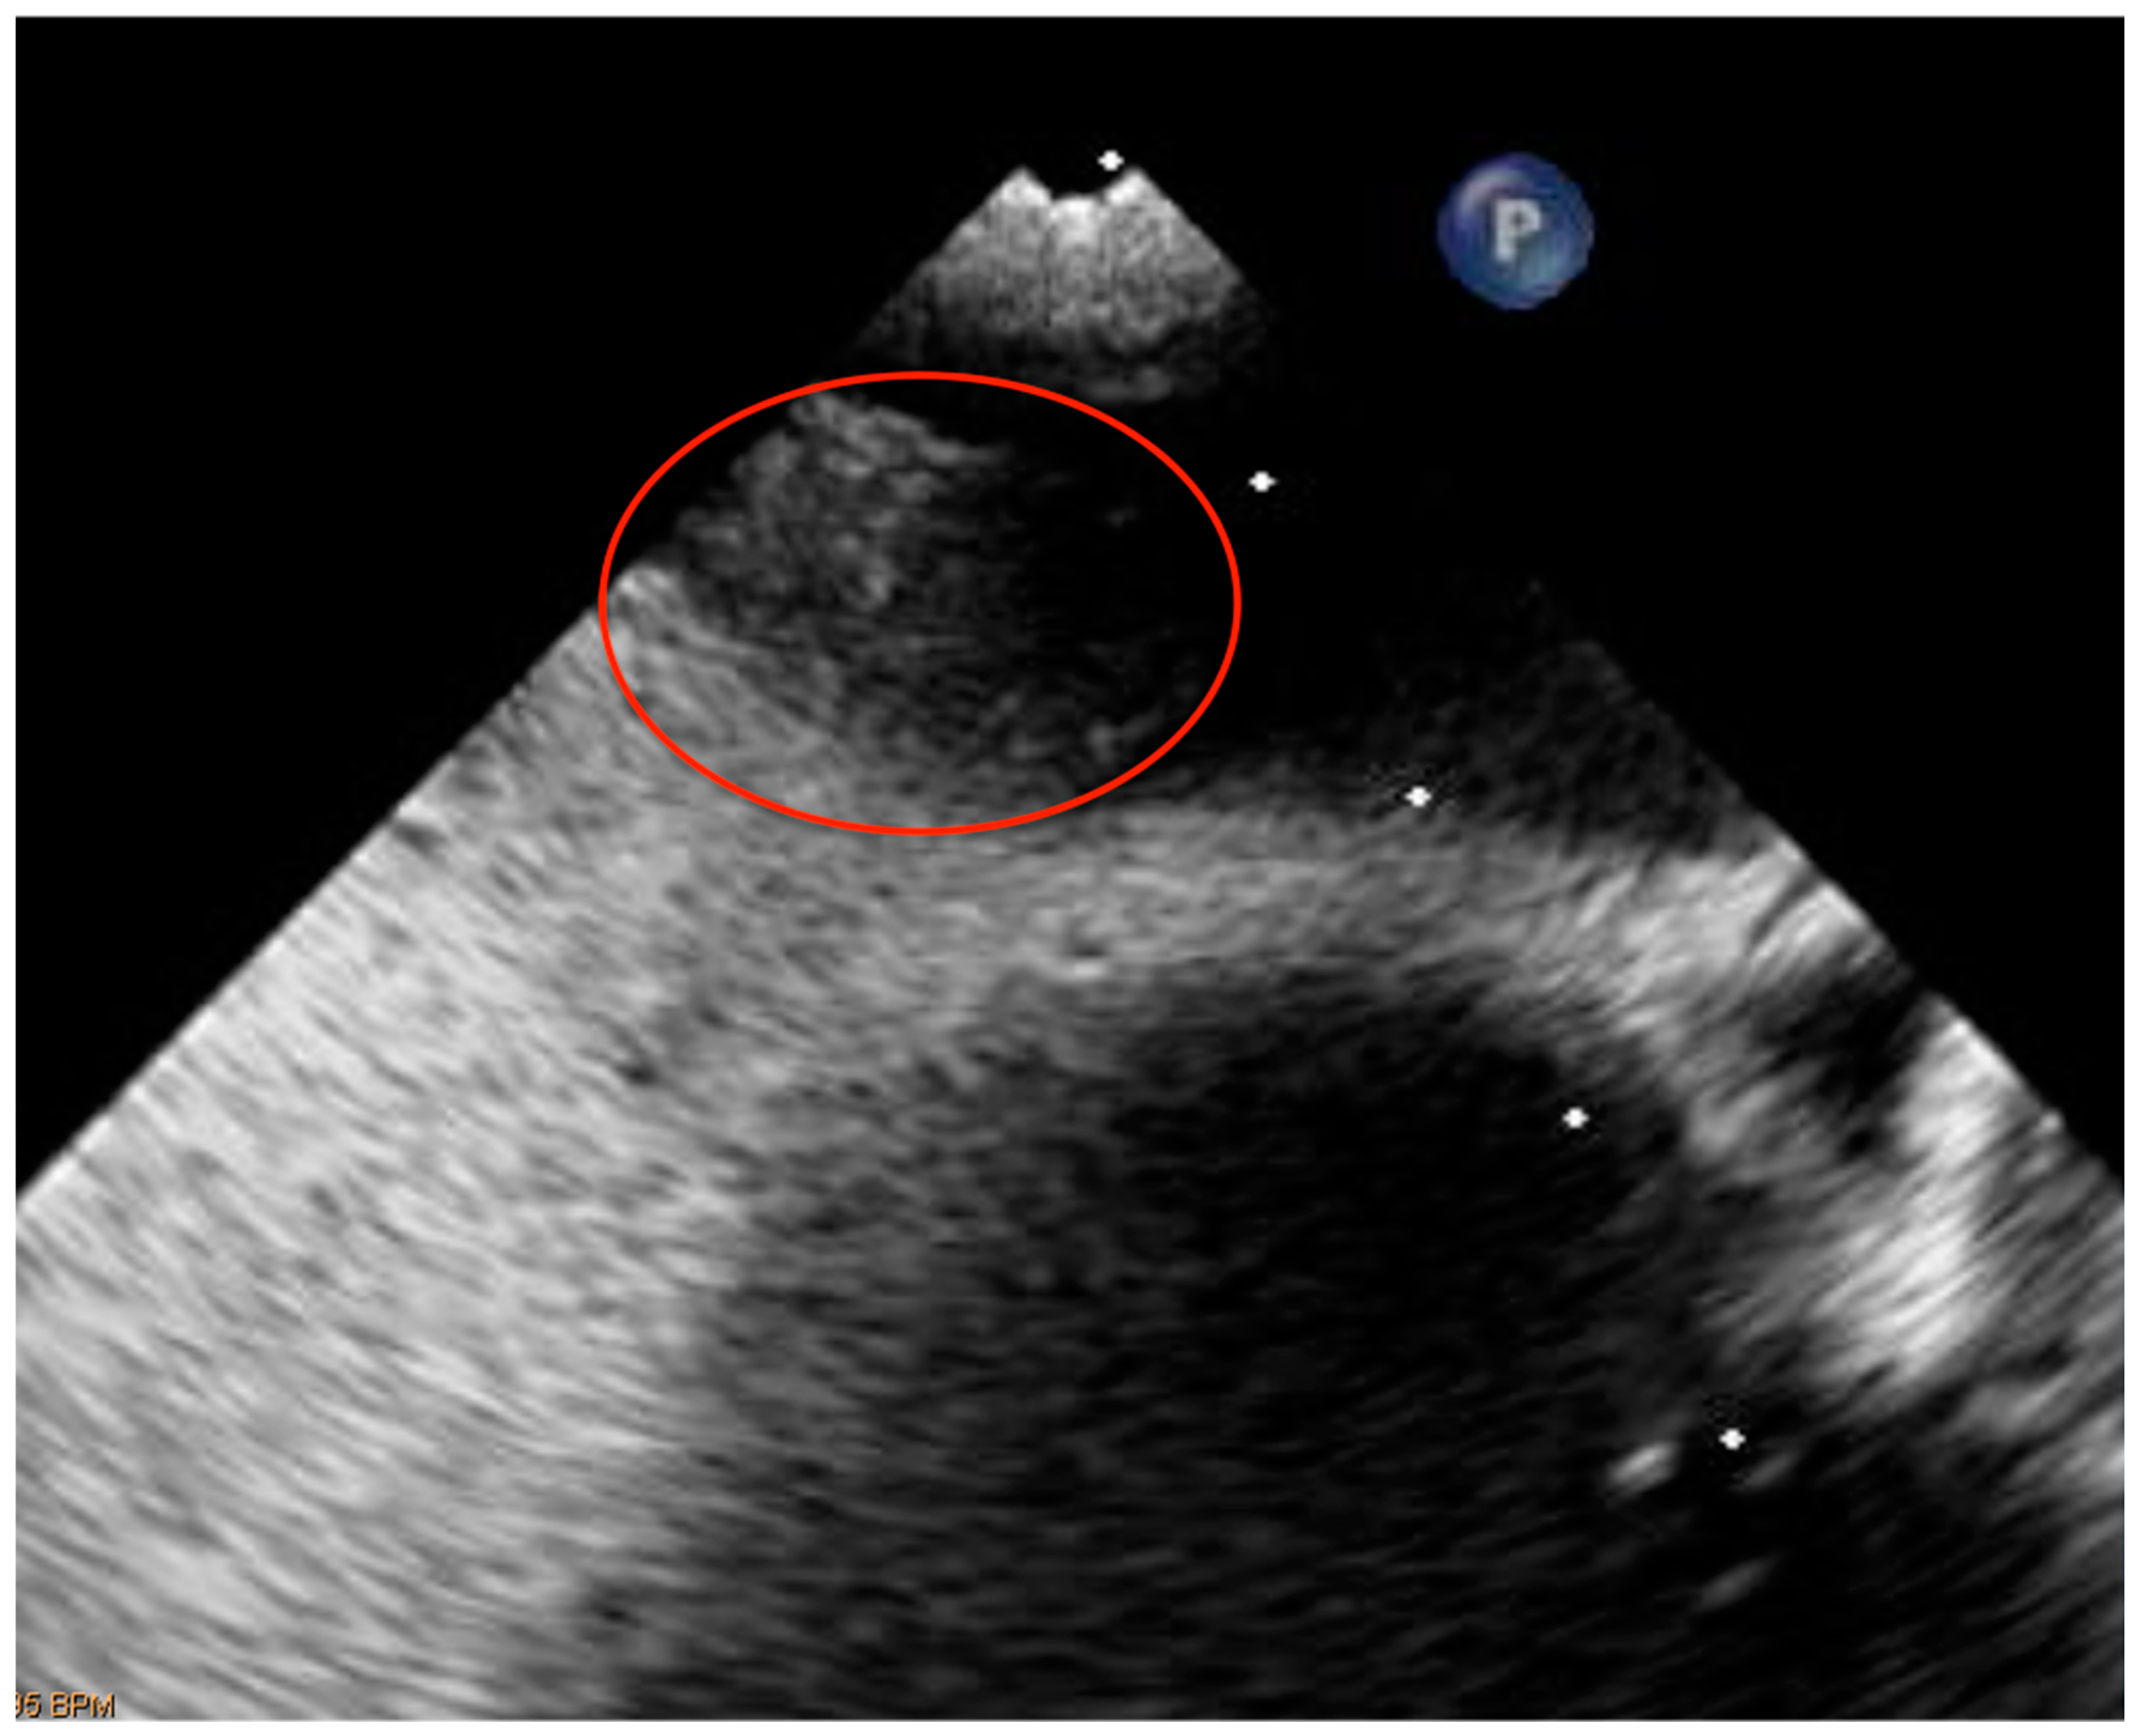

A further contrast transcranial doppler (c-TEE) and contrast transesophageal echocardiogram (c-TCD) for the study of the hemodynamics of the right-to-left shunting were set because the clinical features were suggestive of an ischemic stroke with cardio-embolic genesis (likely due to PFO) [63,64,65,66]. The c-TCD “was indicative of permanent high grade intra-cardiac shunt” and the c-TEE confirmed the existence of a “large PFO” [63,64,65,66] (Figure 3).

Figure 3. The echocardiographic image displays a secundum atrial septum defect with patent foramen ovale (PFO).